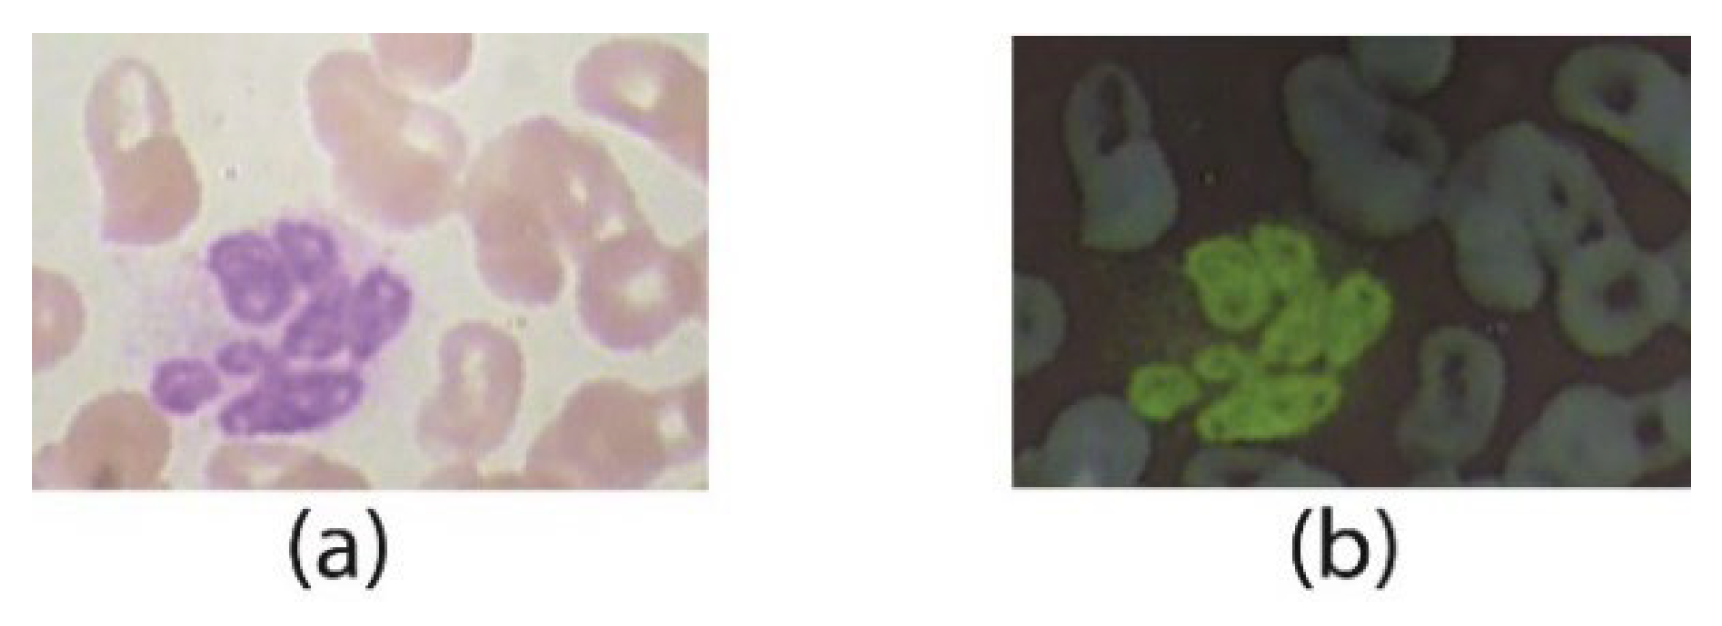

In the adaptive immune system, a major type of lymphocyte, named B-lymphocytes, induce “Y” shape terminal antibodies. When evaders (bacteria/virus) enter into the cell, these antibodies act to neutralize by completely coating the outer surface with other different types of antibodies. This phenomenon is called opsonization. Coated cell acts as a signal transmitter to other immune system cells, i.e., neutrophils. Neutrophils come into contact with the coated cell and digest the pathogen. As a result, infection (pathogen) enters into the cell body [5]. If the antibody structure is not healthy enough to destroy/digest the pathogen completely, it infects the inner cell body and the nucleus as well. Although the medical literature is extensive, here, we are only discuss the intensity-based visualization of WBCs. Infection generation depends upon the structure of the WBC nucleus. This infection may cause diseases of different types depending upon the infection class and level of infection. WBCs are mainly classified into two main classes: (a) Granulocytes and (b) Agranulocytes. In the Granulocytes the subtypes are (i) neutrophils, (ii) eosinophils, (iii) basophils, and (iv) lymphocytes. On the other hand, Agranulocytes consist of only one main type, that is Monocytes. Existing work contains various white blood datasets such as Raabin, LISC, BCCD, and ALL-IBD, with sub-classes [1] such as (a) Lymphocytes, (b) Monocyte, (c) Neutrophil (circular shaped nucleus) (d) Eosinophils, and (e) Basophil (as shown in Figure 1). Basophil is only 1% of the total WBC content in the body and has no contribution to infection generation. In this work, only four of the above types, excluding basophil, are used for WBC image analysis.

Figure 1.

WBC classes: (a) eosinophil (b) neutrophil (c) basophil (d) monocyte (e) lymphocytes.